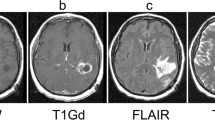

The growing interest in machine learning (ML) in healthcare is driven by the promise of improved patient care. However, how many ML algorithms are currently being used in clinical practice? While the technology is present, as demonstrated in a variety of commercial products, clinical integration is hampered by a lack of infrastructure, processes, and tools. In particular, automating the selection of relevant series for a particular algorithm remains challenging. In this work, we propose a methodology to automate the identification of brain MRI sequences so that we can automatically route the relevant inputs for further image-related algorithms. The method relies on metadata required by the Digital Imaging and Communications in Medicine (DICOM) standard, resulting in generalizability and high efficiency (less than 0.4 ms/series). To support our claims, we test our approach on two large brain MRI datasets (40,000 studies in total) from two different institutions on two different continents. We demonstrate high levels of accuracy (ranging from 97.4 to 99.96%) and generalizability across the institutions. Given the complexity and variability of brain MRI protocols, we are confident that similar techniques could be applied to other forms of radiological imaging.

Pizarro R, Assemlal HE, de Nigris D, Elliott C, Antel S, Arnold D, Shmuel A: Using deep learning algorithms to automatically identify the brain MRI contrast: implications for managing large databases. Neuroinformatics 17(1):115–130, 2019